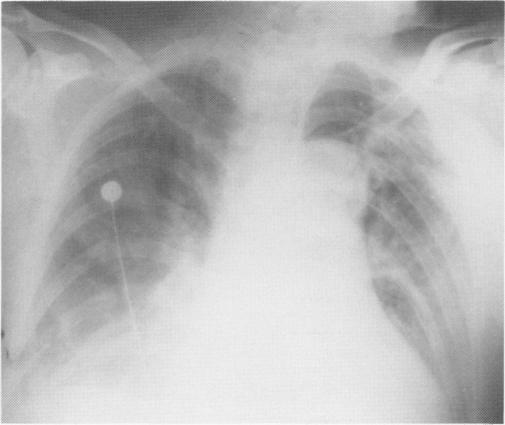

Thirty of 33 patients (ages 18-67) with acute dissection of the ascending aorta underwent surgical intervention. There were four deaths. There were eight male and five female patients and 15 patients were known to be hypertensive. Severe chest pain, widened mediastinum (demonstrated radiographically), and varying degrees of aortic insufficiency were present in each patient. Heart failure was present in 13 patients, numbness and coolness of an extremity in seven patients, and central nervous system changes were present in three patients. The diagnosis in each instance was confirmed by aortography. Three patients treated nonoperatively died during hospitalization following aortic rupture into the mediastinum and pericardium. The remaining 30 patients were managed by insertion of a woven Dacron((R)) graft sutured distal to the coronary arteries and proximal to the origin of the great vessels. This was accompanied with resuspension of the aortic valve in 24 patients and valve replacement in six patients. Each of the latter six patients had a history of aortic valve disease. The goals of the operation were: 1) correction of the accompanying aortic insufficiency, either by valve replacement or resuspension of the valve and 2) placement of a prosthetic graft into the ascending aorta, thereby obliterating the false lumen and preventing involvement of the coronary arteries or rupture into the mediastinum or the pericardium. Hypertensive patients were managed pre- and postoperatively with nitroprusside and then with propranolol HCI, methyldopa, or hydralazine HCI and hydrochlorothiazide. One late death occurred six months after myocardial infarction and a second late death occurred from a presumed cardiac arrhythmia. One patient had a femorofemoral graft two months after the initial operation and another patient has mild aortic insufficiency. It is concluded that prompt surgical management is mandatory in acute ascending aortic dissection, and in most patients aortic valve competency can be re-established with resuspension of the valve preventing the added morbidity associated with a prosthetic valve. Four patients have been followed for five years and additional follow-up data will better define long-term survival.

33例年龄在18至67岁之间的升主动脉急性夹层患者中,30例接受了手术干预。其中4例死亡。患者中有8名男性和5名女性,已知15例患有高血压。每位患者均出现严重胸痛、纵隔增宽(影像学显示)以及不同程度的主动脉瓣关闭不全。13例患者出现心力衰竭,7例患者出现肢体麻木和发凉,3例患者出现中枢神经系统改变。每例诊断均经主动脉造影证实。3例非手术治疗的患者在住院期间因主动脉破裂进入纵隔和心包而死亡。其余30例患者通过在冠状动脉远端和大血管起源近端缝合编织涤纶(R)移植物进行治疗。24例患者同时进行了主动脉瓣再悬吊术,6例患者进行了瓣膜置换术。后6例患者均有主动脉瓣疾病史。手术目标为:1)通过瓣膜置换或瓣膜再悬吊纠正伴发的主动脉瓣关闭不全;2)在升主动脉置入人工血管移植物,从而消除假腔并防止冠状动脉受累或破裂进入纵隔或心包。高血压患者术前和术后使用硝普钠治疗,然后使用盐酸普萘洛尔、甲基多巴或盐酸肼屈嗪及氢氯噻嗪。1例患者在心肌梗死后6个月出现晚期死亡,另1例晚期死亡推测为心律失常所致。1例患者在初次手术后2个月进行了股-股人工血管搭桥术,另1例患者有轻度主动脉瓣关闭不全。结论是,升主动脉急性夹层必须及时进行手术治疗,在大多数患者中,通过瓣膜再悬吊可重建主动脉瓣功能,避免人工瓣膜相关的额外发病率。4例患者已随访5年,更多的随访数据将更好地确定长期生存率。